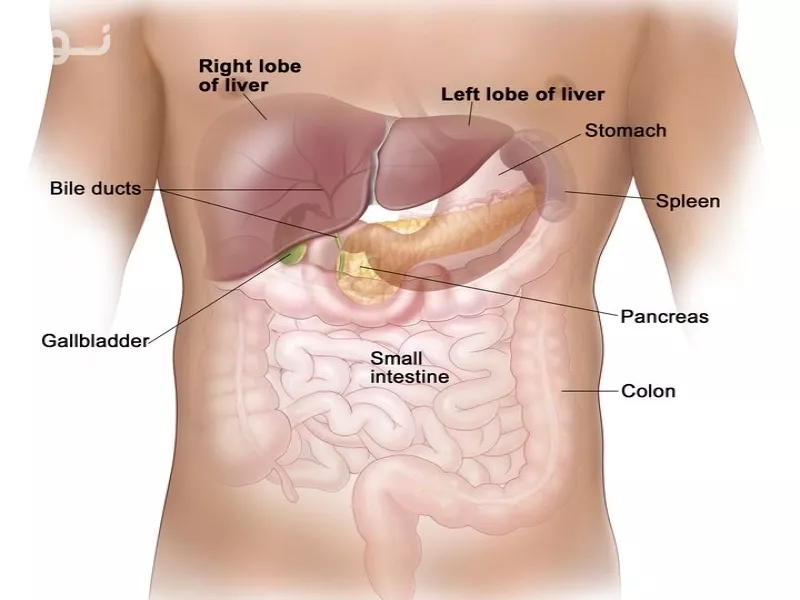

درد کبد کجای بدن است؟ این سوالی است که بسیاری از افراد هنگام احساس ناراحتی در ناحیه شکم به دنبال پاسخ آن هستند. کبد، یکی از حیاتیترین اندامهای بدن، در سمت راست فوقانی شکم و زیر دندهها قرار دارد. این عضو مسئول تصفیه سموم، تولید صفرا و متابولیسم مواد مغذی است.

محل دقیق کبد در بدن کجاست؟

موقعیت آناتومیکی کبد:

- سمت راست بالای شکم (درست زیر قفسه سینه)

- محدوده بین دندههای ۵ تا ۱۰ سمت راست

- در مجاورت اندامهایی مانند:

- کیسه صفرا (در زیر کبد)

- دیافراگم (در بالا)

- کلیه راست (در پشت)

نکته حیاتی تشخیص درد کبد:

درد کبد معمولاً به صورت:

| مکان اصلی | → | راست فوقانی شکم |

| انتشار درد | → | شانه راست | بین کتفها | ناحیه پشتی |

در ۲۰% موارد ممکن است درد به صورت مبهم در کل شکم احساس شود!

محل صحیح درد کبد:

- زیر دندههای سمت راست

- عمق ۵-۷ سانتی متری از پوست